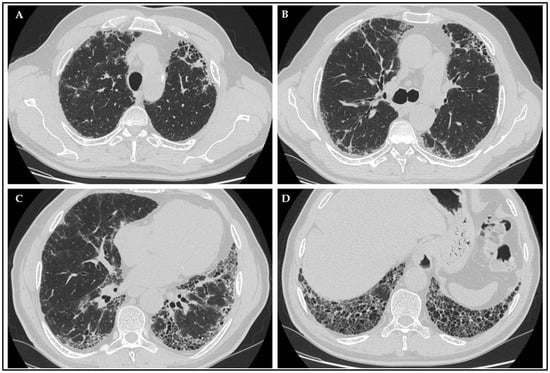

Patients performed chest HRCT, defined as computed tomography (CT) following specific protocol and slice thickness ranging between 0.625 mm and 1.25 mm, scheduled at least annually or when considered clinically necessary. Images were evaluated by a radiologist with expertise in ILD pattern definition. An example of a typical radiological UIP pattern found in the study cohort is shown in Figure 2.

Figure 2.

Radiological presentation of a case of IPF patient with p-ANCA positivity, showing a UIP pattern characterized by typical signs as honeycombing (D), traction bronchiectasis (B,C), subpleural and basal predominant distribution (A–D).